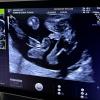

Узи 16 недель,прикрепляю